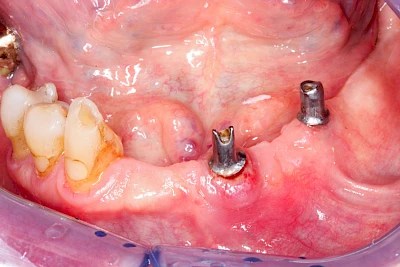

Bei Implantaten – also operativ eingebrachten künstlichen Zahnwurzeln – kann der Körper die Bakterien auch nicht so gut abwehren. Hier spricht man im Fall einer Entzündung von einer Peri-Implantitis, also einer Entzündung um das Implantat herum.